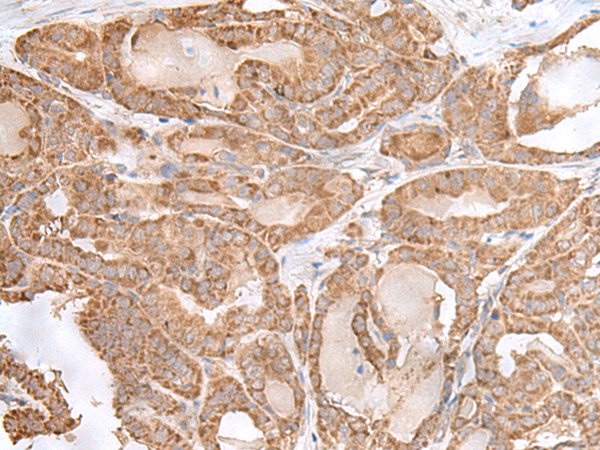

The image is immunohistochemistry of paraffin-embedded Human thyroid cancer tissue using 47712(RPL28 Antibody) at dilution 1/35. (Original magnification: 200)